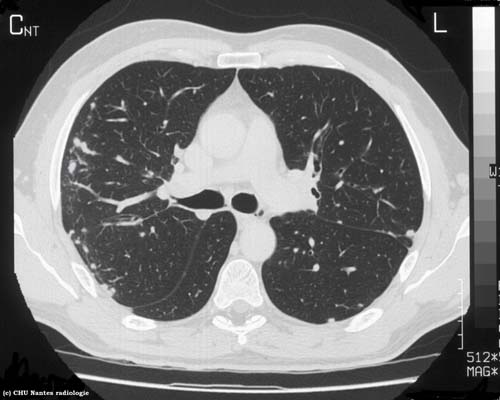

Syndrome interstitiel nodulaire

légendes